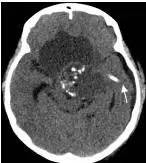

病例1:患儿男性,9岁。因反复出现意识丧失、视力下降半年收入院。入院后CT及 MRI显示颅内有形态不规则、“超大型”的颅咽管瘤,最大径约10厘米,见图1、图2。

图1.术前CT显示典型的囊性颅咽管瘤